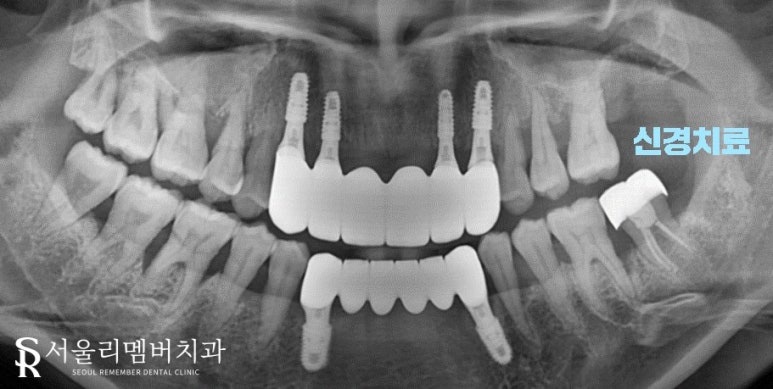

상, 하악 전치부 임플란트

구치부 염증 치아 발치 (# 27 # 38)

신경치료 ( # 37)

전치부 임플란트 식립을 위해 남아있는 조직들을 깨끗하게 없애주었습니다.

혹시라도 남아있게 된다면.. 추후 수술 실패 혹은 부작용의 원인이 될 수 있기 때문이죠.

완전히 제거됨을 확인한 다음 인공치근의 역할을 할 픽스처를 심어드렸습니다.

잇몸의 상태가 별로 좋지 않았기에 기존 조직과 단단히 결합될 수 있을까 걱정이 되었는데요.

다행히 별문제 없이 심을 수 있었네요. 치유지대주까지 부착한 뒤에 어금니 염증이 심한 곳들을 뽑았습니다.

한군데 치아는 그나마 살릴 수 있었기에 신경치료를 진행하기로 했습니다.

이전 과정과 똑같이 깨끗하게 발치를 한 뒤에 근관을 깨끗하게 청소, 소독, 밀폐를 진행하여 끝냈습니다.